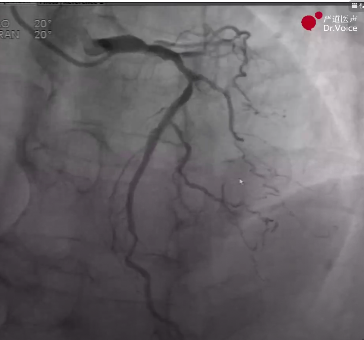

8、在IVUS指导下完成支架植入,最终造影显示血管恢复通畅,分支均保留,未见夹层及穿孔。

RCA远端残余狭窄

RCA最终造影效果